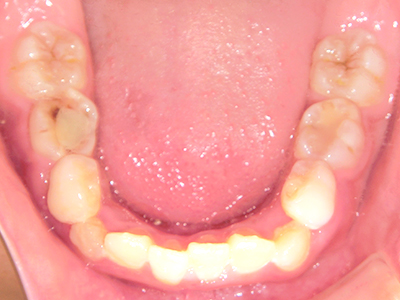

歯並びの相談に来られるお子様は、口呼吸をしているケースが多く、これが歯並びに大きな影響を与えています。

↓ - さまざまな不正咬合が生じる

ないき歯科クリニックでは、上あごの成長不足を補い、鼻呼吸を獲得しつつ歯列を整え、将来のお口をより健康な状態にすることをゴールに定める矯正治療をおこなっています。